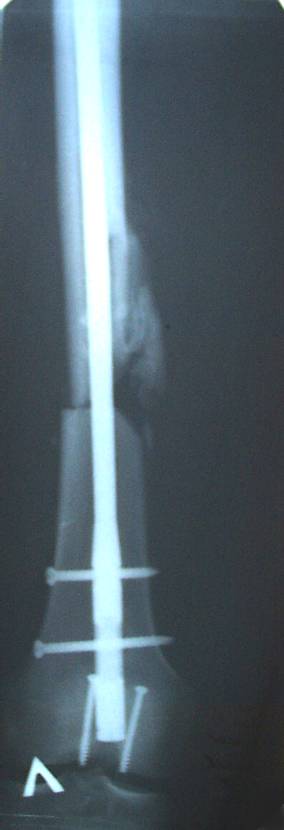

Уважаемый Сергей, избрав вариант DHS плюс ретроградный гвоздь Вы явно обезопасите себя от проблем, связанных с введением штифта через trochanteric fossa. Очень это может быть проблематично, Вы правы. Поэтому DHS плюс ретроградный гвоздь - спокойно выполнимый вариант, особенно в "чужом" отделении. Схожий свой случай из далёкого теперь уже 1999г. прилагаю, только вместо канюлированных винтов у Вас будет DHS (VHS). А если антеградный гвоздь - то только из тех, что предназначены к введению через верхушку вертела. И это тоже выполнимо, но сложнее. Мне так кажется.

Уважаемый Сергей Витальевич! Мы в похожем случае выбрали вариант DHS + DFN. Правда из 4 кортикальных винтов накладки DHS - 2 пришлось вводить монокортикально - уперлись в штифт.. На конечный результат это не повлияло. Ссылка здесь.

К сожалению, послеоперационных снимков в <цифре> нет. Сразу не сделали, а затем <благодарный> больной исчез <из поля зрения>.